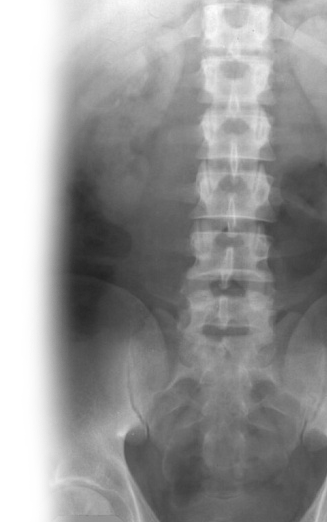

Рентгенография почек и мочевыводящих путей Рентгенография почек и мочевыводящих путей

Рентгенография почек и мочевыводящих путей

Рентгенография почек и мочевыводящих путей – важный метод визуализации почек, мочеточников и мочевого пузыря.

С помощью рентгенографии определяется положение почек, определяется наличие камней в мочевыделительной системе.